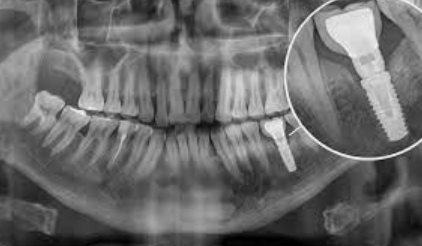

1단계 - 초기 상담: 환자는 치과 의사와 상담을 진행합니다. 의사는 어금니의 상태를 평가하고, X-레이나 CT 스캔을 통해 뼈의 상태를 확인합니다. 이를 토대로 의사는 어금니 임플란트가 적합한 치료 방법인지 판단하며, 필요한 어금니 임플란트 가격을 예상할 수 있습니다.

2단계 - 수술: 치과 의사는 어금니 부위에 조심스럽게 구멍을 내고 임플란트를 삽입합니다. 그 후, 임플란트 주위의 뼈와 임플란트가 안정적으로 결합되도록 치유를 위한 기간을 마련합니다. 이 과정은 일반적으로 수 주에서 몇 개월까지 소요될 수 있습니다.

또한, 어금니 임플란트 시술 후에는 10-20주 사이에 골유착 상태를 확인해야 합니다. 통증, 감염 여부, 출혈 여부, 임플란트 주변 뼈의 손실 여부 등을 확인하여 식립이 잘 되었는지 판단합니다. 이를 통해 어금니 임플란트의 성공 여부를 확인할 수 있습니다.